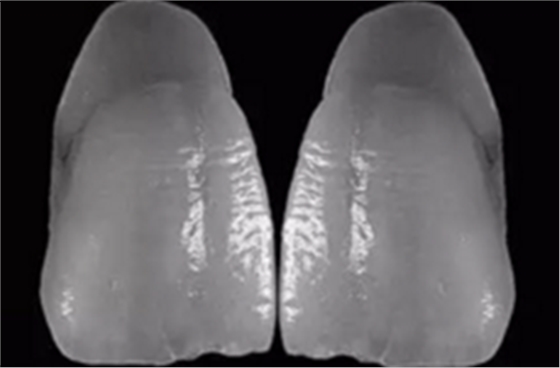

14、在工作模完全就位的義齒

15、在檢測(cè)模上可以看出左上1頸線(xiàn)有誤差